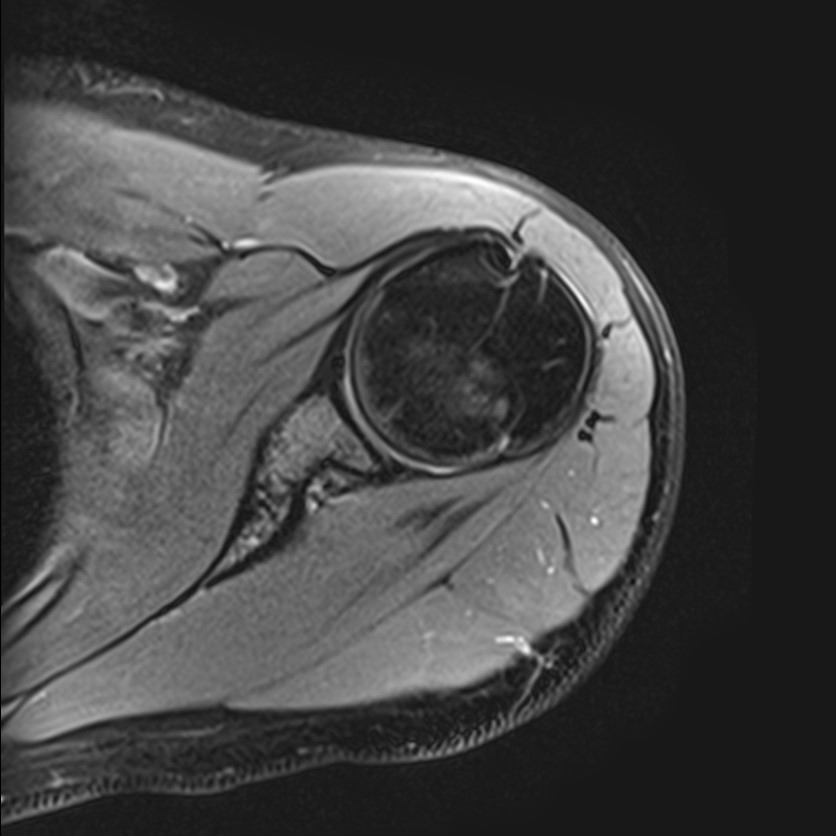

Метод МРТ позволяет оценить состояние всех анатомических областей плечевого сустава,  включая костную структуру, суставную капсулу, полость сустава с выстилающей его синовиальной оболочкой, связки, сухожилия, мышцы и окружающие мягкие ткани.

В клинике «Доступная медицина» исследование проводится на современном высокопольном томографе закрытого типа TOSHIBA VANTAGE TITAN 1,5 Тесла с превосходной  разрешающей способностью, которая обеспечивается высокой индукцией магнитного поля. Аппарат выполняет сканирование послойно в различных плоскостях и на основе этого создает 3D-изображения с высочайшей точностью и достоверностью, что позволяет эффективно ставить диагноз и назначать необходимое лечение.

Магнитно-резонансная томография позволяет выявлять следующие заболевания плечевого сустава:

• Травмы плечевого сустава, различные переломы, при этом наиболее часто встречаются вывихи, что обусловлено анатомией сустава. Нередко травмы сустава с разрывом связок и сухожилий ведут в дальнейшем к развитию нестабильности плечевого сустава и могут стать причиной формирования привычных вывихов.